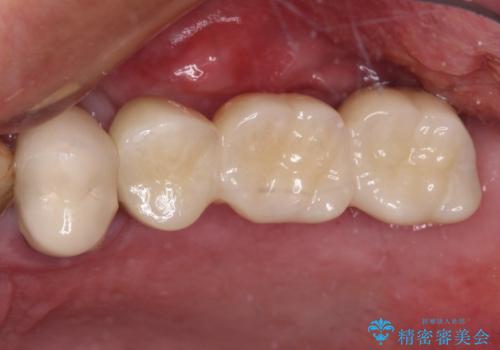

左側は大臼歯2本と小臼歯1本が欠損しているため、インプラント2本を治療したブリッジ、右側は中間欠損であり、前後の歯も加療が必要であったためブリッジによる補綴治療を行うこととしました。

治療後の現在は、より長い期間安定した状態を維持していただくため、就寝時マウスピースを装着するようお願いしております。